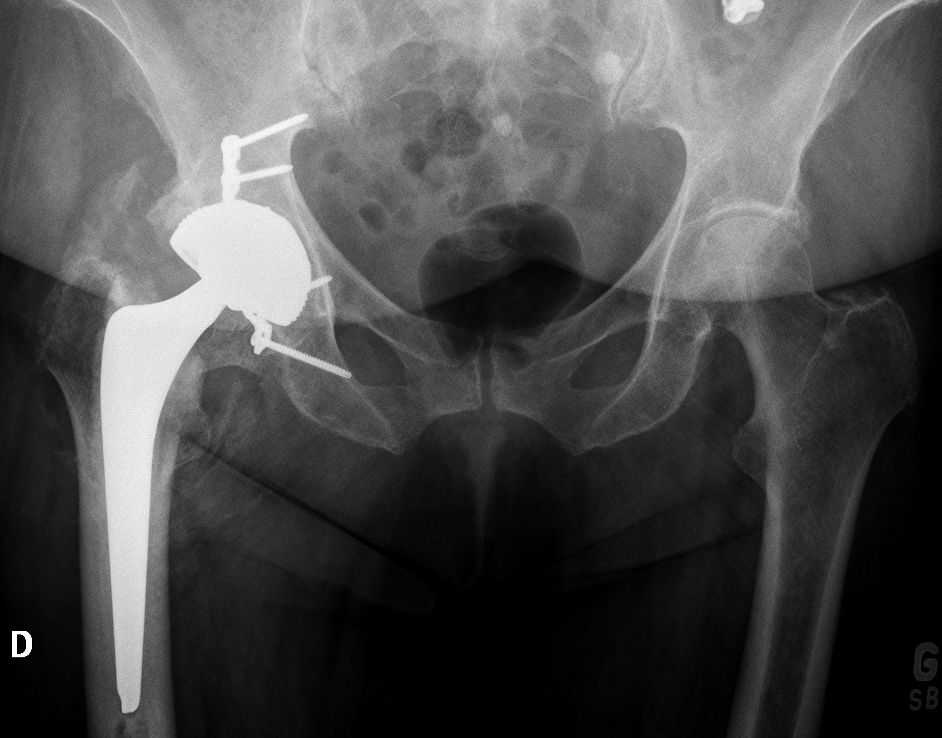

The popularity of CoC bearings has increased worldwide in the last decade, thanks to evidence of better wear resistance and biocompatibility when compared to other materials. However, LDH CoC THAs require a thin metallic acetabular shell to optimize the bearing diameter/cup diameter ratio. Therefore, to minimize the risk of liner fractures due to incorrect liner assembly in a deformed metallic shell, CoC LDH cups are manufactured pre-assembled and then implanted as a monobloc component. We started using LDH CoC in 2011 and implanted >3500 Maxera cups (Zimmer, Warsaw, USA, Fig. 2).

The shell is made of titanium Ti-6Al-4V alloy with a thin layer of titanium vacuum plasma spray coating (Ti-VPS) applied to the exterior. The BIOLOX delta taper liner is pre-assembled and secured into the shell using an 18° taper angle. This implant has outer diameters ranging from 42mm to 66mm and inner diameters ranging from 32mm to 48mm.

Using an LDH THA allows unrestricted movement after THA, for all types of surgical approaches. Vendittoli’s group in Canada does not impose any postoperative ROM restrictions for the posterior surgical approach, as it simplifies the patient education process, boosts their confidence during rehabilitation, and facilitates bilateral procedures[15,16]. LDH monobloc DM is especially interesting for many older women with large thighs and a small acetabular cavity (<50mm, Fig. 7).

In these cases, standard bearing diameters are prone to instability. With an LDH, a DM design provides optimal implant stability for these not-so uncommon patients. Moreover, with LDH we do not impose any activity restrictions in the long term. LDH CoC THA offers a major benefit for many active individuals since they can return to their regular jobs (e.g. plumber, roof worker, police officer, fireman) as well as for those who want to practice sports like rock climbing, kayaking, water skiing and martial arts.